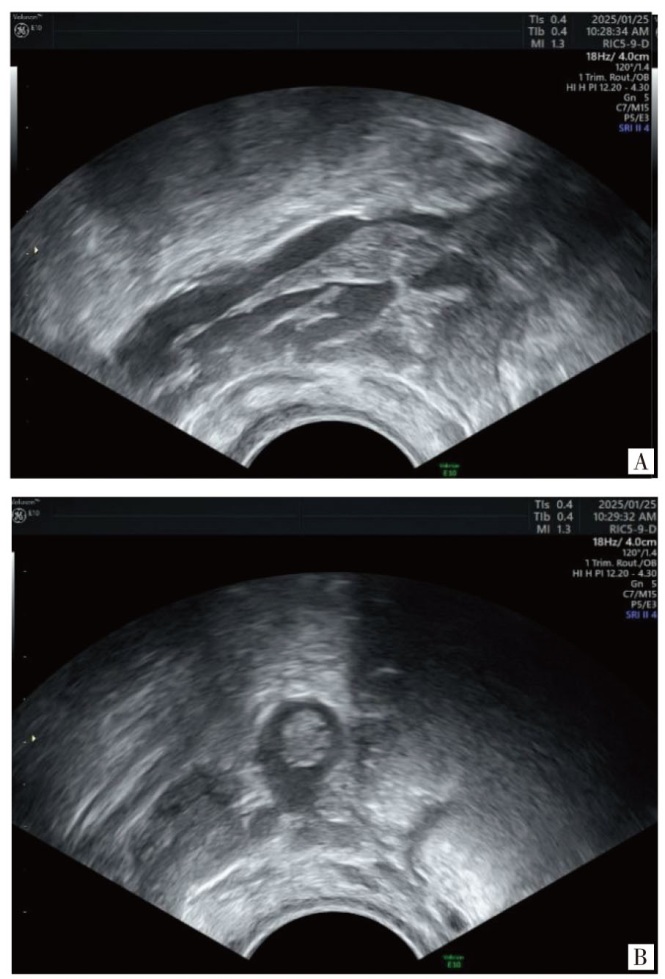

妊娠合并盆腔静脉丛血栓形成是一种较严重的妊娠并发症。该病发病率低,临床表现不典型,一般不易察觉。报告1例辅助生殖技术妊娠后,于孕40+ d常规彩色多普勒超声检查发现盆腔静脉丛内团块,超声提示早孕合并盆腔静脉丛血栓形成,后经给予低分子肝素抗凝和地屈孕酮保胎治疗后血栓消失,母婴预后良好。报道此病例旨在提高超声医师及临床医师对本病的认识,对临床化验及家族史可疑存在“易栓症”的孕妇,超声检查既要包括宫内胚胎发育情况、附件区情况,又要注意盆腔静脉丛的检查,对盆腔静脉丛血栓形成做到早期诊断和早期治疗,改善母胎结局。

Pelvic venous plexus thrombosis complicating pregnancy is a relatively severe pregnancy-related complication. This disease has a low incidence rate and atypical clinical manifestations, so it is generally difficult to detect. We report a case where, after pregnancy achieved through assisted reproductive technology, a mass in the pelvic venous plexus was detected by routine color Doppler ultrasound examination at more than 40 days of gestation. The ultrasound indicated early pregnancy complicated with pelvic venous plexus thrombosis. After anticoagulant treatment with low-molecular-weight heparin and tocolysis treatment with dydrogesterone, the thrombus disappeared, and the prognosis of the mother and the infant was good. The purpose of reporting this case is to improve the awareness of this disease among ultrasound physicians and clinical physicians. For pregnant women with suspected "thrombophilia" based on clinical laboratory tests and family history, the ultrasound examination should include the intrauterine embryonic development, the condition of the adnexa, and also pay attention to the examination of the pelvic venous plexus, so as to achieve early diagnosis and early treatment of pelvic venous plexus thrombosis and improve the maternal-fetal outcomes.